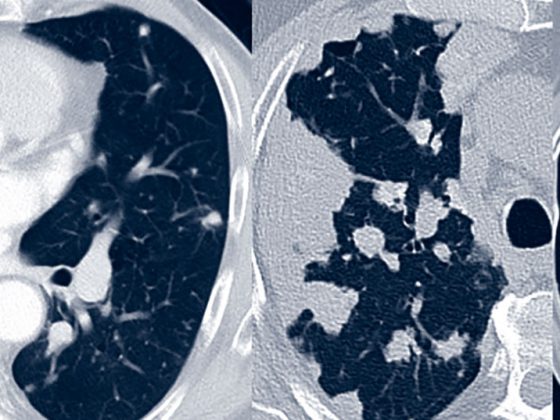

amyloidose_pulmonal

• Seltene Lungenerkrankungen

Pulmonale Amyloidose

• CME-Fortbildung

• Fortbildung

• Pneumologie

• Rx